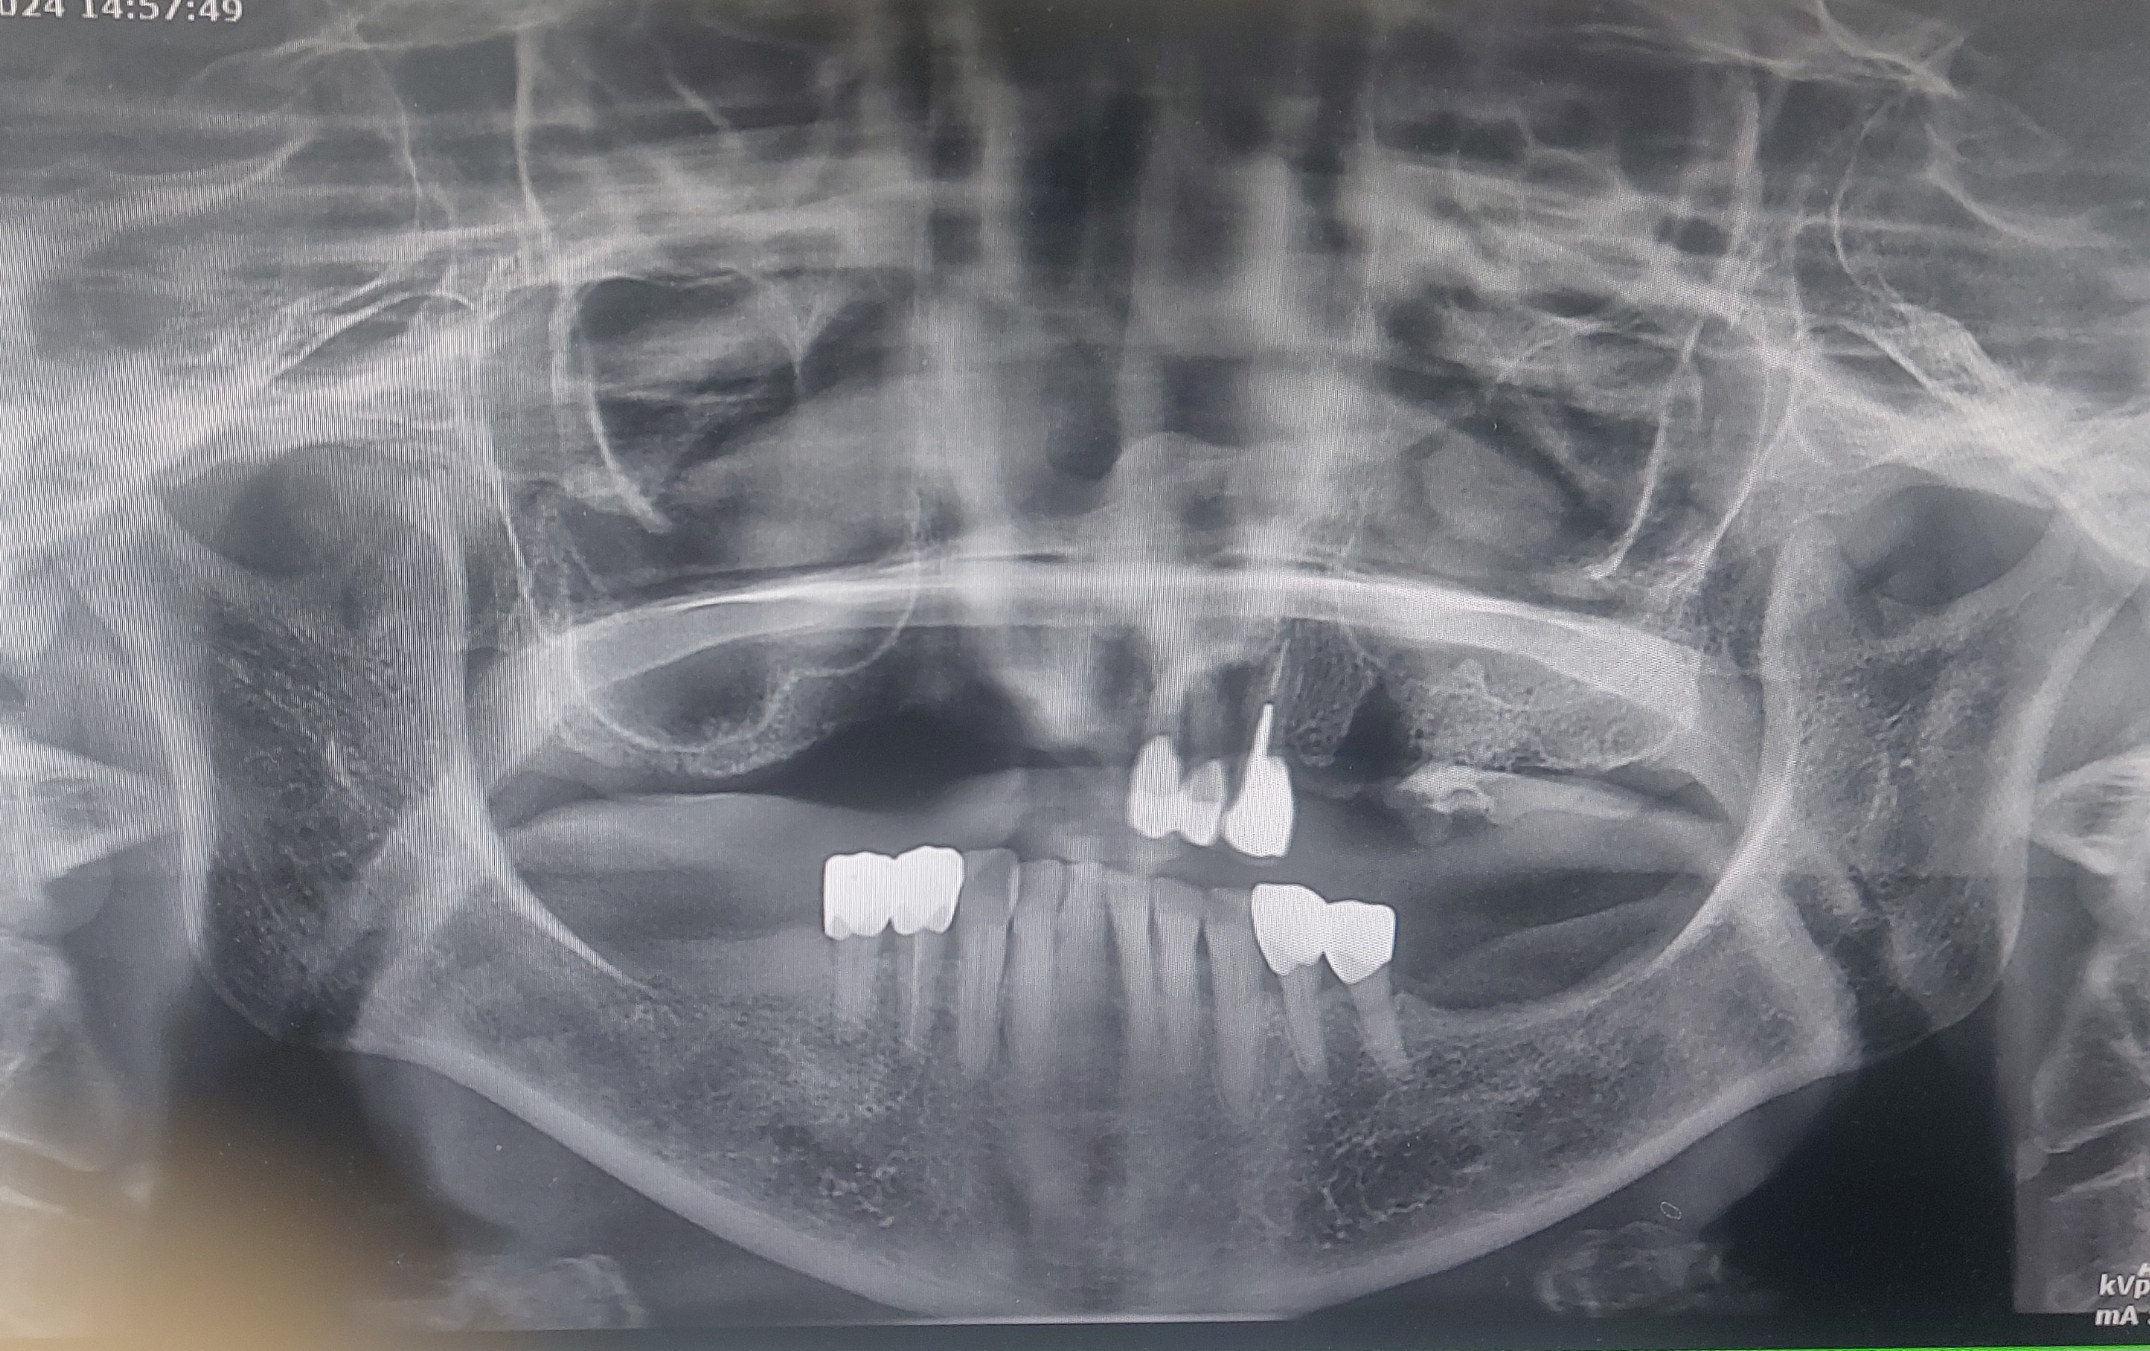

초진 사진입니다.

위에 보시는 것처럼 오른쪽 대구치는 잔존골이 약 3- 5 mm 사이입니다. 그리고 뼈가 방사선 사진 만으로도 많이 위축된 모습이 관찰

됩니다. (방사선 사진은 반대로 보입니다.)